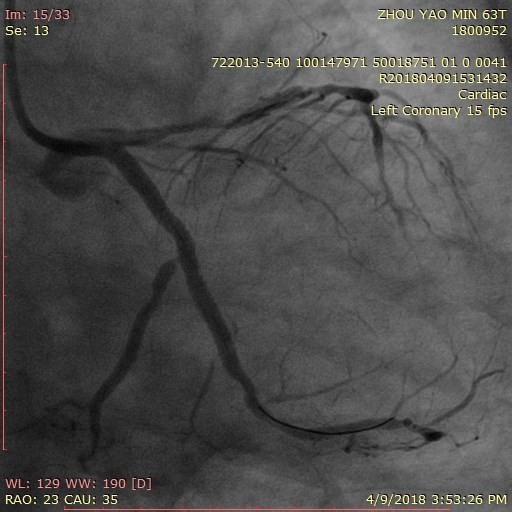

Căn cứ vào kết quả xét nghiệm, chiếu chụp trên, các bác sĩ Trung tâm Tim mạch, Bệnh viện E chẩn đoán bệnh nhân M. bị nhồi máu cơ tim cấp và được chỉ định chụp động và can thiệp động mạch vành cấp cứu.

Kết quả, bệnh nhân bị tắc động mạch vành mũ (LCx), hẹp phức tạp 2 nhánh LAD và RCA. Xác định đây là ca bệnh khó, nặng và phức tạp, cần được can thiệp sớm nên chỉ sau 30 phút kể từ khi vào viện, bệnh nhân Min đã được vào phòng mổ can thiệp cấp cứu kịp thời.

ThS. BS Lý Đức Ngọc – Phó trưởng khoa Nội tim mạch người lớn – Trung tâm Tim mạch – Bệnh viện E cho biết: "Các bác sĩ Trung tâm Tim mạch đã tiến hành can thiệp cấp cứu cho bệnh nhân Min đặt 1 sent động mạch vành vào phần tắc của động mạch vành mũ. Việc tái thông động mạch vành cho bệnh nhân giúp quả tim của bệnh nhân hoạt động bình thường trở lại".

Hình ảnh cơ tim của bệnh nhân M |